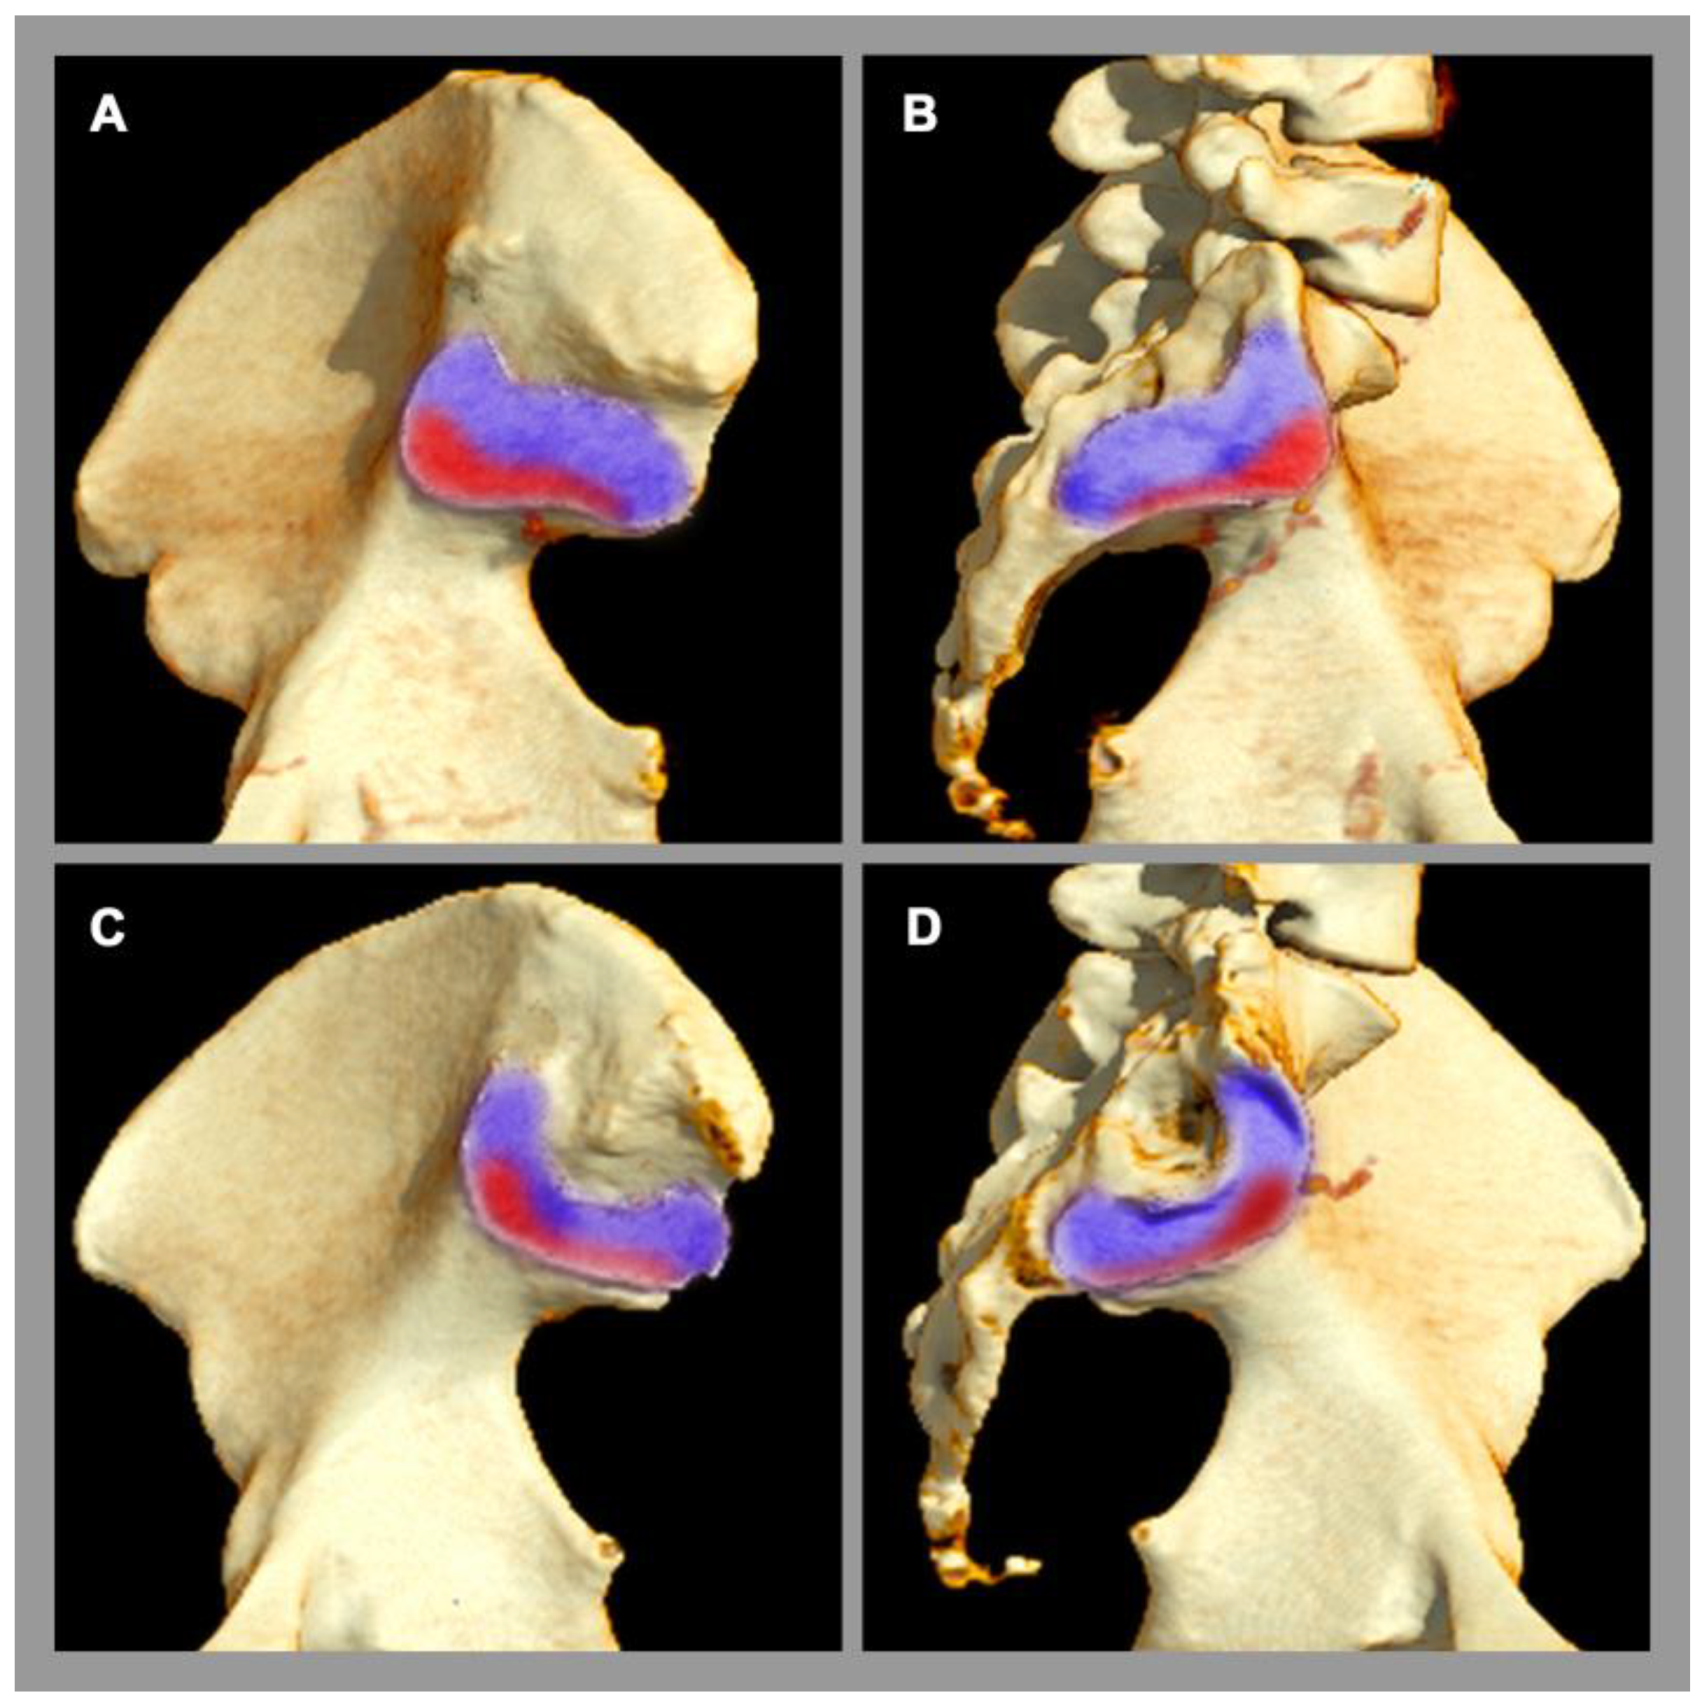

Osteitis condensans ilii is a frequent pathology of the SIJ [5], which is classified as a non-inflammatory disease. Its origin is attributed to mechanical stress and imbalance across the SIJ, e.g., during pregnancy and childbirth [2], causing a chronic stress response. Clinically, affected patients present with chronic back pain, which typically begins before the age of 45 [5]. Osteitis condensans ilii is significantly more common in women than in men, possibly due to the different biomechanical properties of the SIJ and flexible ligamentous structures in the female pelvis [5], especially concerning delivery. The typical imaging finding at the sacroiliac joint is sclerosis and its specific distribution pattern in the anterior and inferior part of the SIJ with a typical triangular shape (also called “hyperostosis triangularis ilii”) [5]. In addition, bone marrow edema can also be seen in osteitis condensans ilii, but this is not specific, since other factors, such as sporting activities, can also lead to bone marrow edema in the SIJ in the region of mechanical stress [54,55], see Figure 3.

Figure 3.

Sacroiliac joint load zones. 3D computed tomography reconstruction. (A,C) Lateral view of the ilium. (B,D) Lateral view of the sacrum. Male pelvis (A,B). Female pelvis (C,D). There are sex differences in the distribution of the load zone (red area) with respect to the rest of the joint surface (purple area). In women, the center of gravity is more ventrally located.